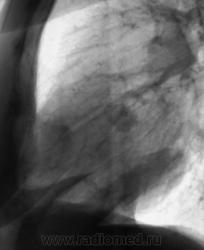

Контроль после флюорографии. Стандартное дообследование.

Ваше мнение уважаемые коллеги?

Mts? Но откуда? Что в анамнезе?